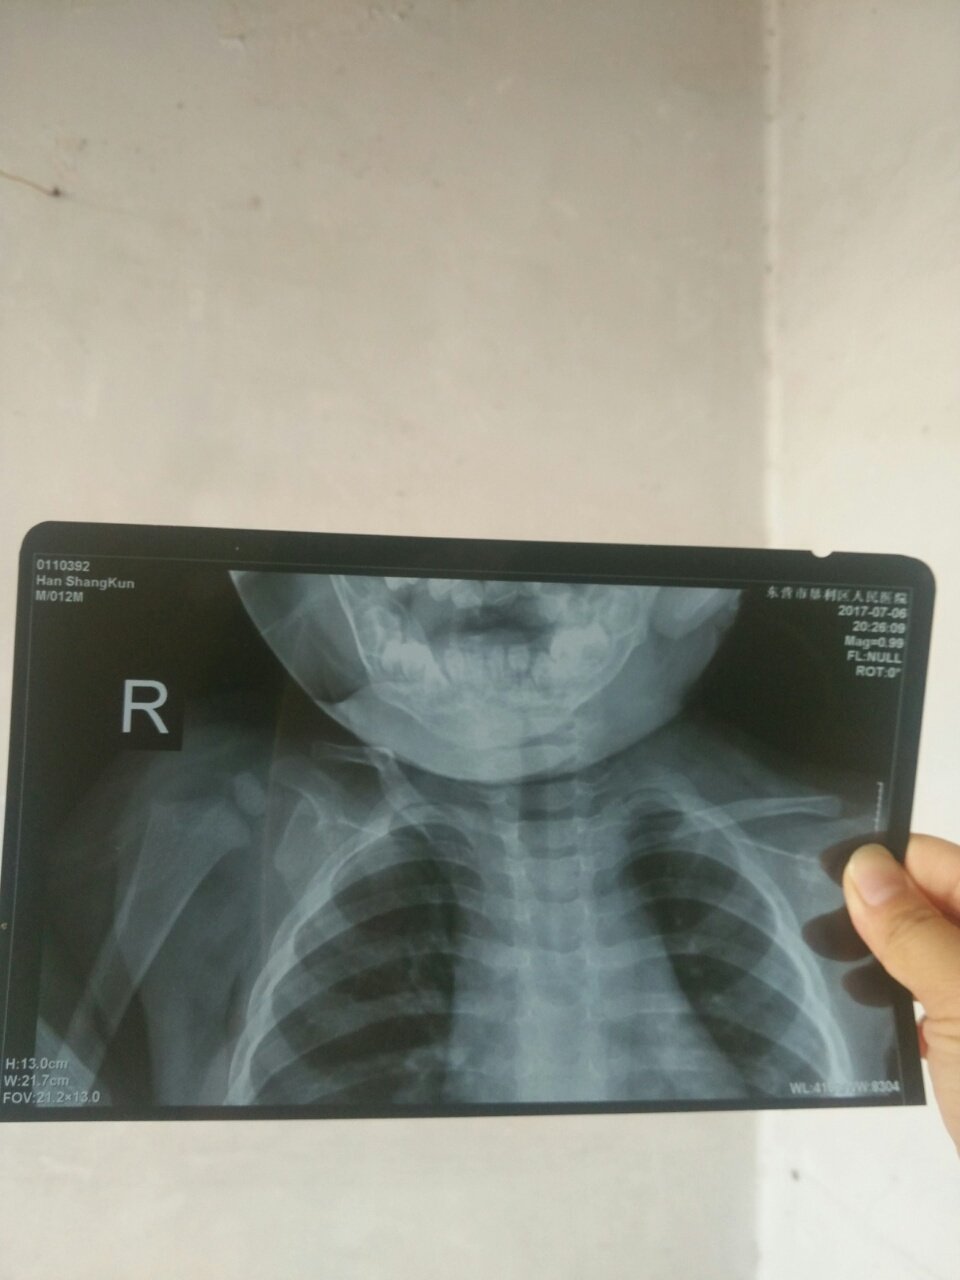

1岁宝宝锁骨骨折,医生让自行修复,一碰到那块,孩子光哭 1岁宝宝锁骨骨折,医生让自行修复,一碰到那块,孩子光哭。 点击展开 151*****652_rH51 2017-07-07 13:45 为您推荐: 其他回答 看医生。??? 151*****643_IlaX 2017-07-08 22:34 肯定啊疼啊 招简直463461463 2017-07-08 21:22 正常,,, 永远牵挂你的人是我 2017-07-07 14:41 听医生的。 细细粒baby 2017-07-07 14:19 保守治疗4--6周即可长好,可用8字套将双臂向后固定。一般不会遗留关节活动受限,骨性愈合后局部有硬结,2--3年平复。可服用止疼药。 cn#afVVuVuVBL 2017-07-07 14:12 加载更多 相关问题 有宝宝一岁锁骨骨折的吗?今天宝宝从床上掉下来,锁骨骨折了心里好难受…去医院医生说自己可以长好,给绑 十三岁孩子在学校误伤同学导致锁骨骨折怎么处理,学校让我出医药费我该承担多少责任呢? 请问一下医生宝宝一岁了,有时哭的时候在肚脐的旁边下一点感觉有肠子下去的一样,问一下医生是疝气还是鞘